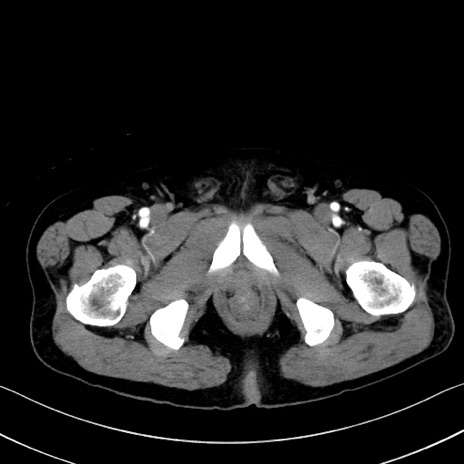

症例35(横断像)

【症例】70歳代 男性

【主訴】腹部膨満、嘔吐

【現病歴】昨日より腹部膨満感出現。本日増悪し、仙痛出現。嘔吐あり、受診。

【既往歴】糖尿病、胆摘後

【身体所見】BP 149/80mmHg、HR 74/min、BT 35.9℃、腹部:膨満、軟、圧痛なし。腸雑音減弱あり。上腹部正中切開瘢痕あり。

【データ】WBC 13500、CRP 1.72